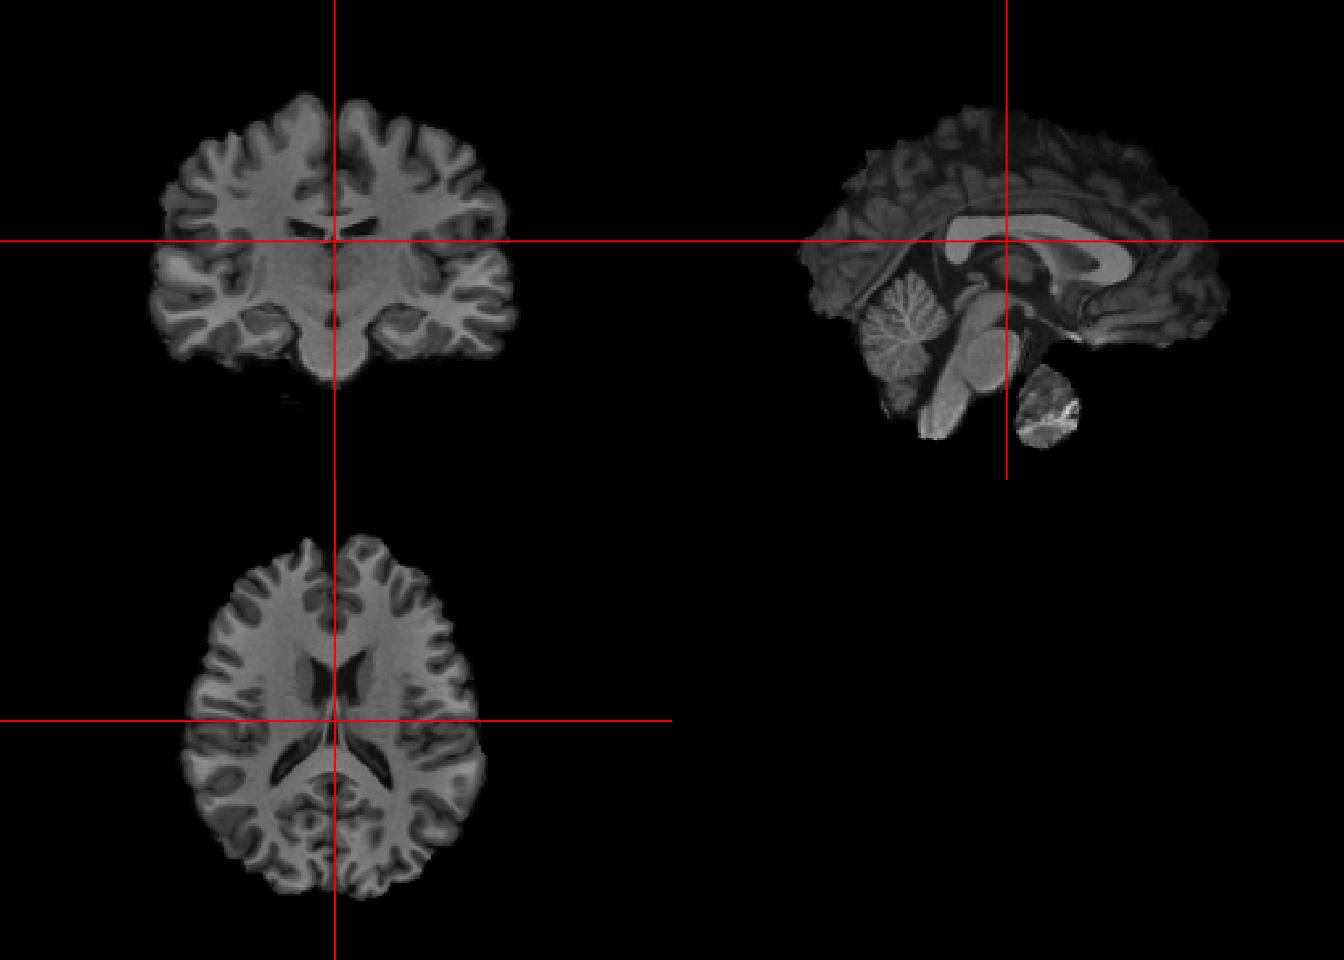

register_img = fslr::flirt(infile = bet2_fast_img,

reffile = template_img,

dof = 6, #for rigid transformation

retimg = TRUE)## Warning in get.fsl(): Setting fsl.path to /usr/local/fsl